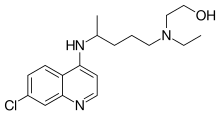

En 1894, Payne, del hospital St. Thomas de Londres, divulgó la utilidad de la quinina en el tratamiento del lupus y señaló una causa vascular como subyacente a la enfermedad. Cuatro años más tarde, el uso de salicilatos en asociación con quinina demostró ser todavía más beneficioso.[12][13]

- Antipalúdicos

- Los antipalúdicos de síntesis, como la hidroxicloroquina, se utilizan principalmente para las manifestaciones cutáneas y articulares, así como para el control general de la enfermedad.[79] La terapia con hidroxicloroquina debería darse a todos los pacientes con LES que no tengan contraindicaciones para este medicamento.[83]